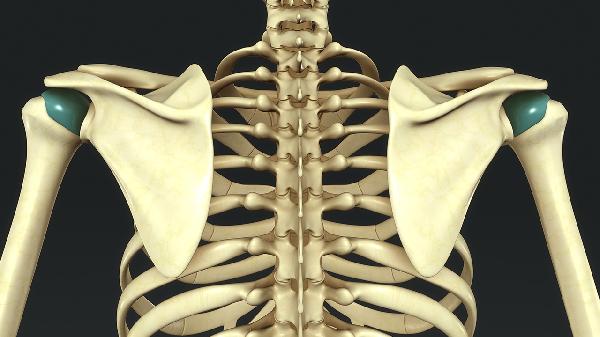

青春期快速生长可能加重漏斗胸或鸡胸,胸骨压迫心脏时会出现心悸、运动耐力下降。微创Nuss手术可植入矫正钢板,胸腔镜手术创伤小,术后2-3年取出固定装置。